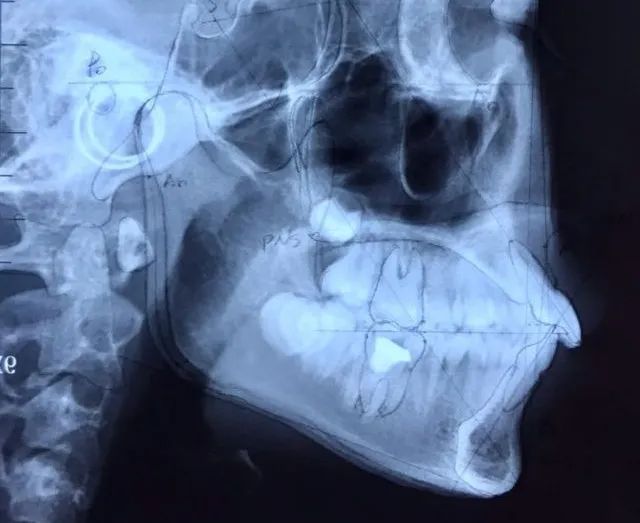

要想确定自己究竟属于牙性还是骨性突嘴,需要到专业医院先通过X光或ct来确诊。牙性突嘴会有明显的牙齿唇倾,而骨性突嘴会显示无牙齿突起和牙体唇倾,而是骨头前倾。接着专业医生会测量求美者的这三个数据:SNB、SNA、ANB角。颌面正常的求美者通常这三个角的角度有一个正常的均值范围,不在该范围内,就可能会有前凸或后缩的情况。

∠SNA:

该角大于正常均值越多,就表现为上颌前凸,侧脸呈凸面型;反之上颌后缩,侧脸呈凹面型。

∠SNB:

该角大于正常值越多就表现为下巴前凸,反之下巴后缩。

∠ANB:

表示求美者的上颌和下颌的前后相对位置关系。该角超出正常均值越多表明上颌前突,反之,代表上颌后缩,或下颌前凸。